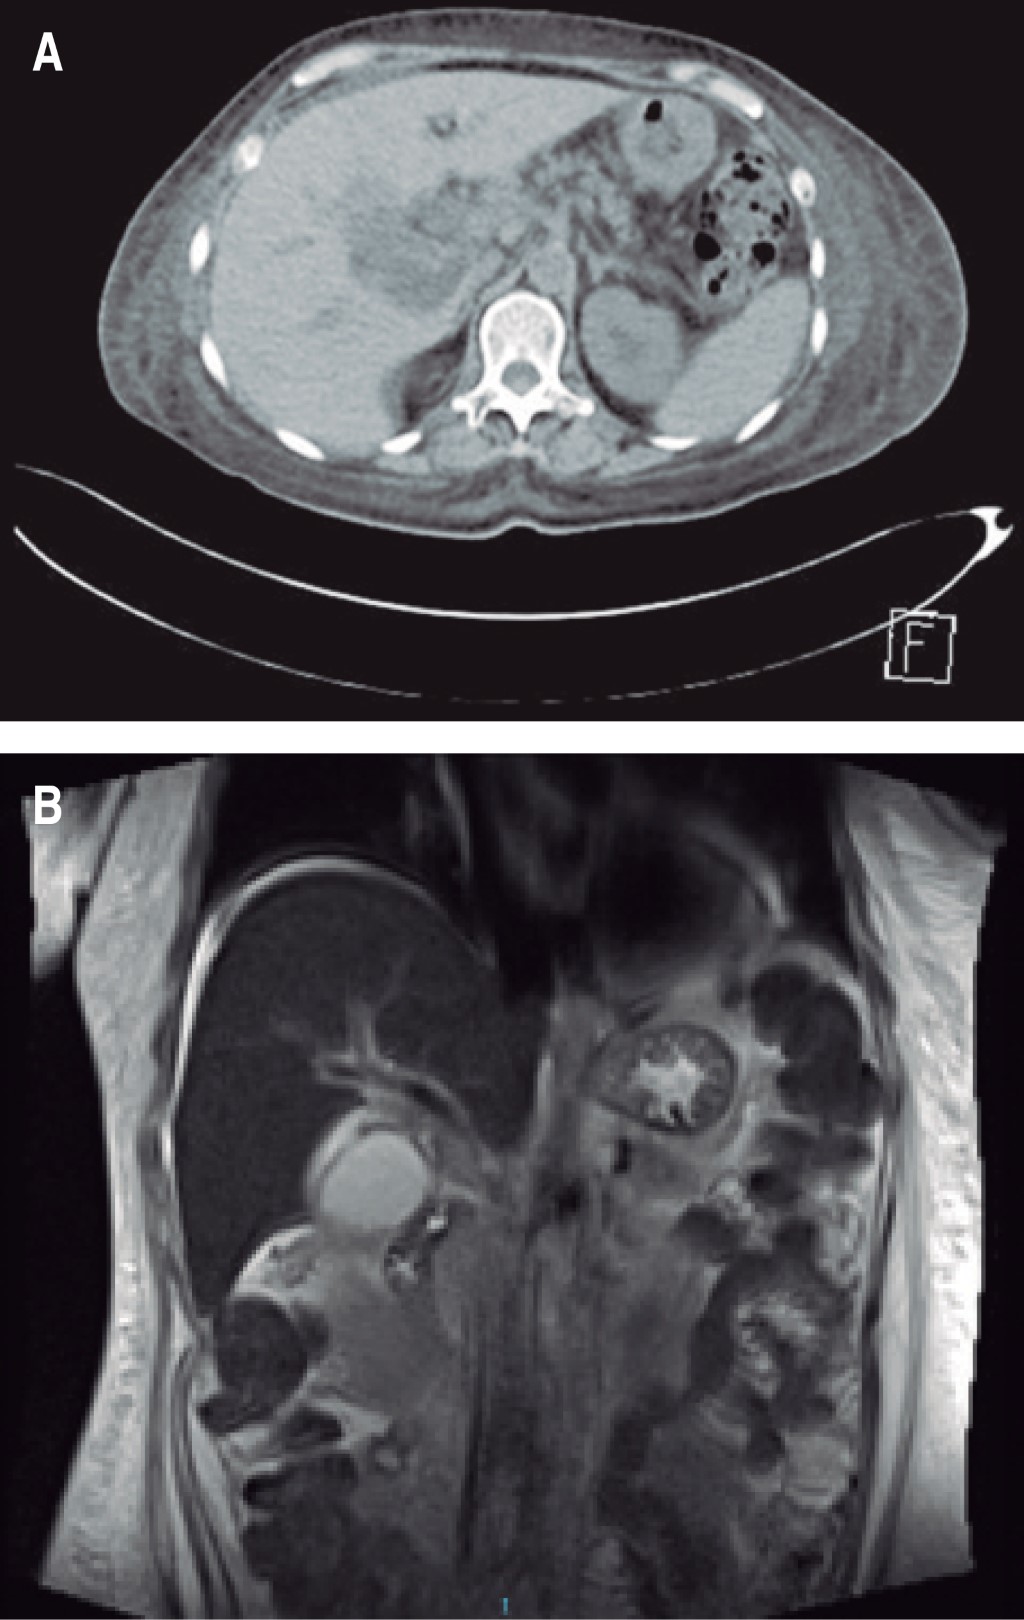

The degree of renal damage was classified according to the creatinine values in the first laboratory test, those at the follow-up and at discharge. Eighty per cent 80%) of the patients were classified in stage III, according to AKIN (Table 2). The imaging study to initiate the approach is with an abdominal ultrasonography scan and to assess the patient's evolution, and abdominopelvic CT scan was requested (Figure 1).

Figure 1